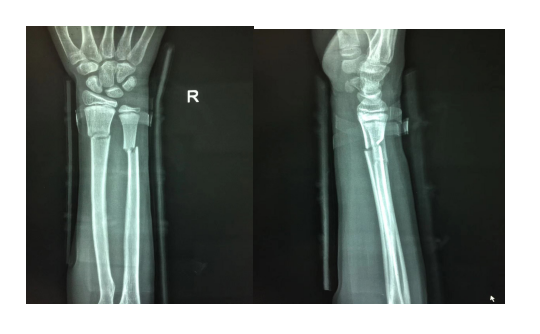

经小儿骨科副主任医师孟祥栋手法复位、夹板外固定,X线光片可见:右尺桡骨远端骨折断端对位对线良好。

本月后复查,见x光片如下:右尺桡骨远端骨折断端对位对线良好,可见骨痂形成。